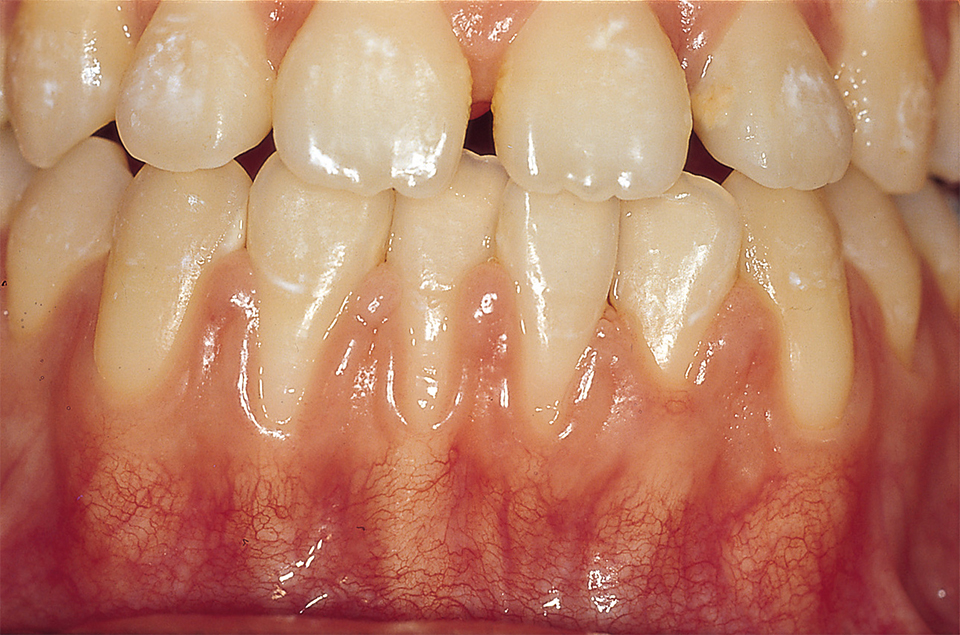

2) ÀÕ¸öÀÇ ¿°Áõ ¹× ÅðÃà

±³Á¤ÀåÄ¡¸¦ ÀåÂøÇϰí ÀÕ¼ÖÁúÀ» °ÔÀ»¸®Çϸé ÀÕ¸öÀÌ º×°í Çǰ¡ ³ª±â ½±½À´Ï´Ù. ÀÌ·± °æ¿ì ÀÕ¼ÖÁúÀ» Ãæ½ÇÈ÷ ÇÏ¸é º°µµÀÇ Ä¡·á¸¦ ¹ÞÁö ¾Ê¾Æµµ Ä¡À¯µÉ ¼ö ÀÖÀ¸³ª Á¤µµ°¡ ½ÉÇϰųª ±¸°À§»ý °ü¸®´É·ÂÀÌ ºÎÁ·ÇÑ °æ¿ì Ä¡ÁÖ, ¿¹¹æÄ¡·á¸¦ ¹Þ¾Æ¾ßÇÕ´Ï´Ù. ÀÕ¸öÀÇ ÅðÃàÀº ³ªÀ̰¡ µé°Å³ª ±¸°À§»ý»óŰ¡ ÁÁÁö ¾ÊÀ» ¶§ ³ªÅ¸³ª¸ç ¶§·Î´Â À߸øµÈ ÀÕ¼ÖÁú ¹æ¹ý¿¡ ¿øÀÎÀÌ ÀÖ½À´Ï´Ù(±×¸²2).